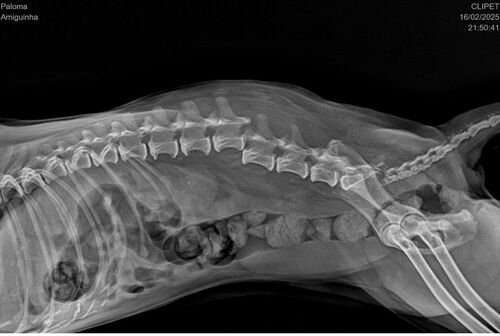

Oi, esta é a Amiguinha, nossa cachorrinha de 12 anos, ela já esta idosa e é ceguinha, infelizmente ela sofreu um acidente onde fraturou a coluna e perdeu os movimentos das patinhas traseiras, precisamos fazer esta cirurgia o mais rápido possível (ate quarta feira 19/02) na esperança dela voltar a andar. Peço ajuda de todos que puderem ajudar com qualquer valor, e quem puder compartilhar ja ajuda muito tambem. Estamos em uma corrida contra o tempo Por favor ajudem!